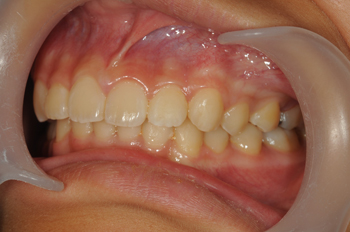

Ⅰ期治療(拡大床による骨格治療)で、少しワイヤーを使うだけでここまでキレイに並びました。

After

小学校3年生から始めて中学1に上がるまで期間はかかりましたが、キレイに並んで本人もご家族もご満足いただけました。お子様の歯並びは、将来のお子様の歯の健康や心身の健康に大きく関わってきます。また、歯並びが悪いとどうしても磨き残しや食べかすが詰まりやすくなり、若いうちからむし歯によって歯が悪くなることが多々有る上、判断が遅れⅡ期治療からになると、抜歯を余儀なくすることもあり得ます。